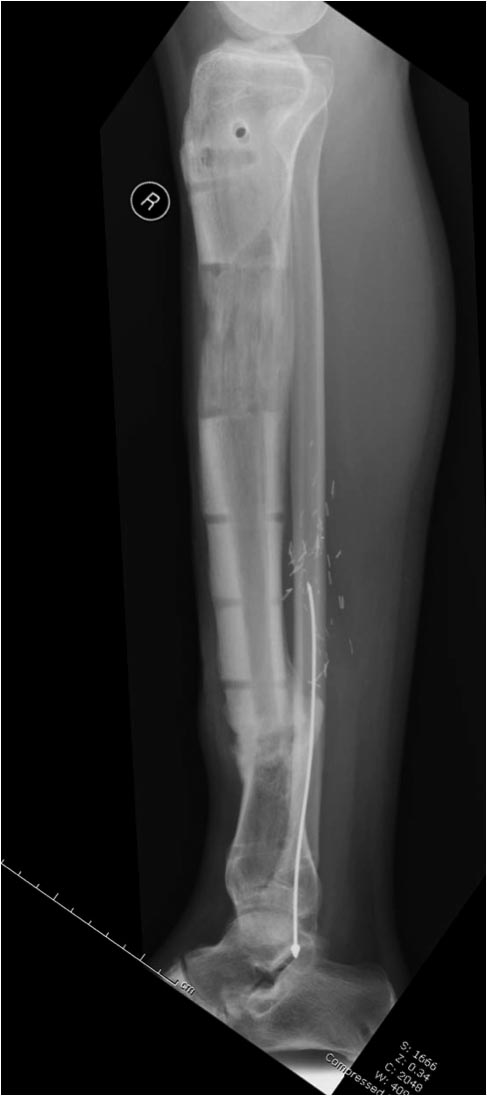

Данный случай не огнестрельная рана, а результат мотоциклетной аварии. Независимо от повреждения при таких обширных дефектах мягких и костной тканей применяется схожая тактика. Как видно, после нескольких I&D для создания “pseudo membrane” применили цилиндрический блок из цемента. Дефект мягких тканей закрыли свободным Anterior Thigh Graft. Из малого доступа цилиндр удален небольшими кусочками, а пространство заполнили бусами для освобождения пространства. По мере приближения регенерата освободили пространство удалением бус через небольшой разрез. Этап созревание регенерата можно было ускорить усилением интрамедуллярным гвоздем, но решили закончить методом Илизарова.

Теперь по поводу данного случая - “спейсер” из цемента предупреждает инфекцию и сохраняет пространство. Но вместо “бус” “цилиндрическая форма” более удобная, вокруг нее образуется ровная трубчатая поверхность “псевдо-мембраны” что в дальнейшей позволит закрыть небольшие дефекты “графтом” или во время удлинения облегчает скольжение регенерата как по трубке.

Из истории Афганской войны известно, что "доктрина убирать все фрагменты с последующим замещением дефекта" привела к долгим восстановительным операциям. А проведенные работы в США в начале 90х по фиксации огнестрельных переломов показали, что классические методы фиксации гвоздем намного лучше, чем сложные восстановительные операции. Чем быстрее создается стабильность, тем лучше, и при сохранении длины костей переломы срастаются в те же сроки и с очень низким процентом осложнений.